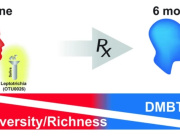

Here, we developed a method of predicting biological age of the host based on the microbiological profiles of gut microbiota using a curated dataset of 1,165 healthy individuals (3,663 microbiome samples).

Our predictive model, a human microbiome clock, has an architecture of a deep neural network and achieves the accuracy of 3.94 years mean absolute error in cross-validation.

This approach has allowed us to define two lists of 95 intestinal biomarkers of human aging. We further show that this list can be reduced to 39 taxa that convey the most information on their host’s aging.

Overall, we show that (a) micro biological profiles can be used to predict human age; and (b) microbial features selected by models are age-related.